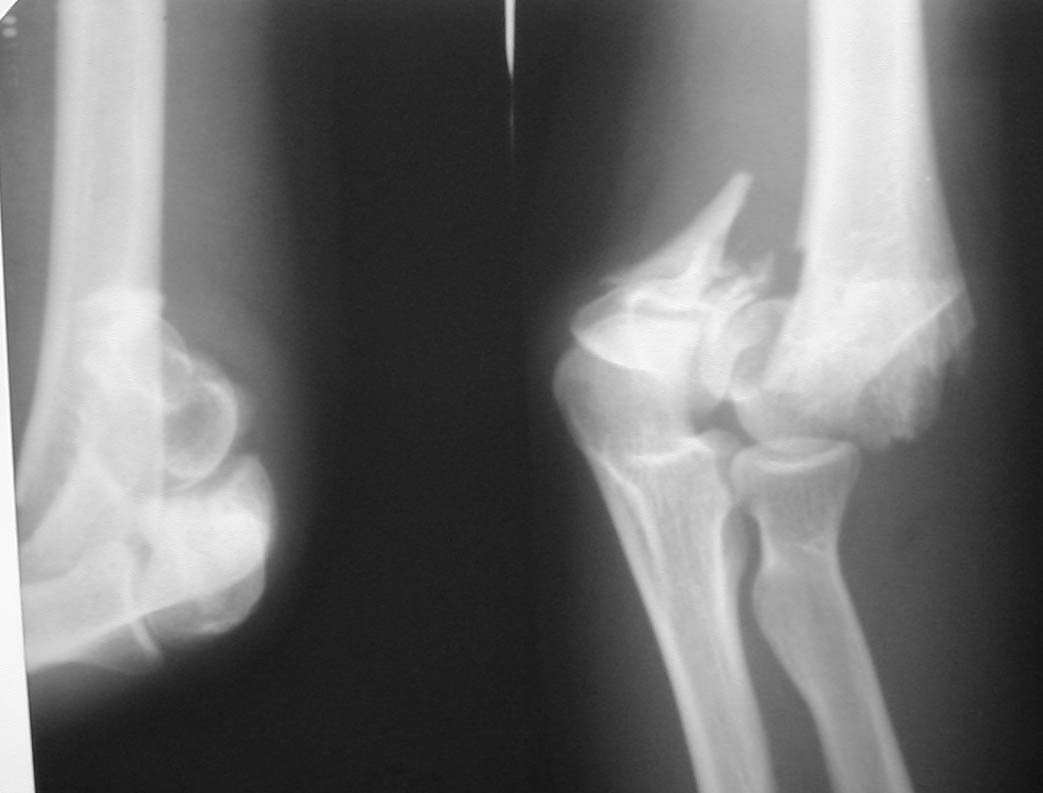

Женщина, 37 лет. Травма в результате падения на улице. Закрытый многооскольчатый перелом дистального метаэпифиза левой плечевой кости со смещением. Неврологических и сосудистых нарушений не выявлено.Лечение? Если внешняя фиксация, то - каков монтаж АВФ? Сейчас пациентка на скелетном вытяжении.С уважением,А.В.Владзимирский

До лечения